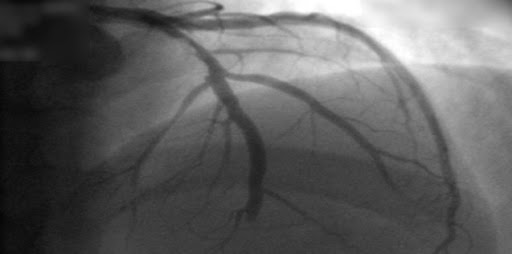

Intervención coronaria percutánea en angina crónica estable: un ensayo clínico doble ciego

21 diciembre 2023

En pacientes con angina estable que recibían poca o ninguna medicación antianginosa y tenían evidencia objetiva de isquemia, la intervención coronaria percutánea resultó en una puntuación de síntomas de angina más baja (una media de 2,7 puntos menos en una escala de 79 puntos) que un procedimiento con placebo, lo que indica un mejor estado de salud con respecto a la angina. New England Journal of Medicine, 21 de diciembre de 2023.